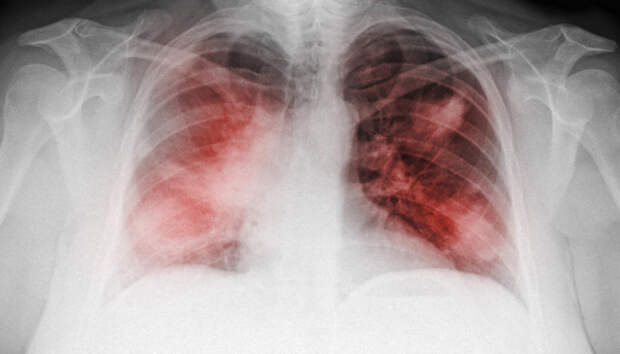

Всем пациентам с воспалением легких неоднократно проводится исследование на COVID-19 Одиннадцать человек за сутки госпитализированы с внебольничной пневмонией в Карелии, сообщает оперштаб по борьбе с распространением коронавирусной инфекции. Летальных исходов за прошедшие 24 часа в республике не зафиксировано.

Всем пациентам с пневмонией неоднократно проводится исследование на COVID-19. Начиная с 1 апреля, с внебольничной пневмонией госпитализированы […] The post Одиннадцать человек с пневмонией госпитализированы в Карелии first appeared on Информационное Агентство 365 дней.